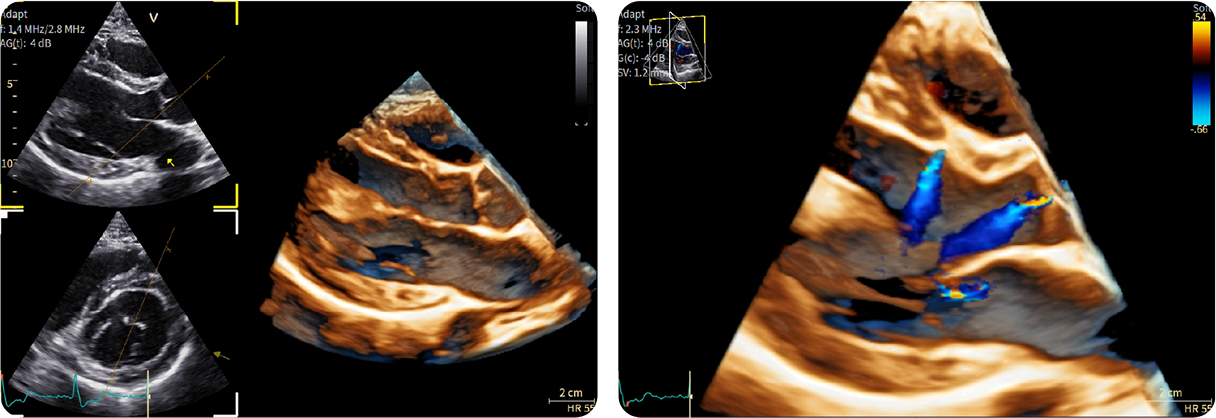

Caso condiviso da Saima Mushtaq

Paziente con anamnesi di malattia coronarica e pregresso impianto di stent sulla discendente anteriore sinistra.

Per prima cosa, esamina l'intera scansione. Concentrati sul tronco comune e sulla porzione prossimale della discendente anteriore sinistra.